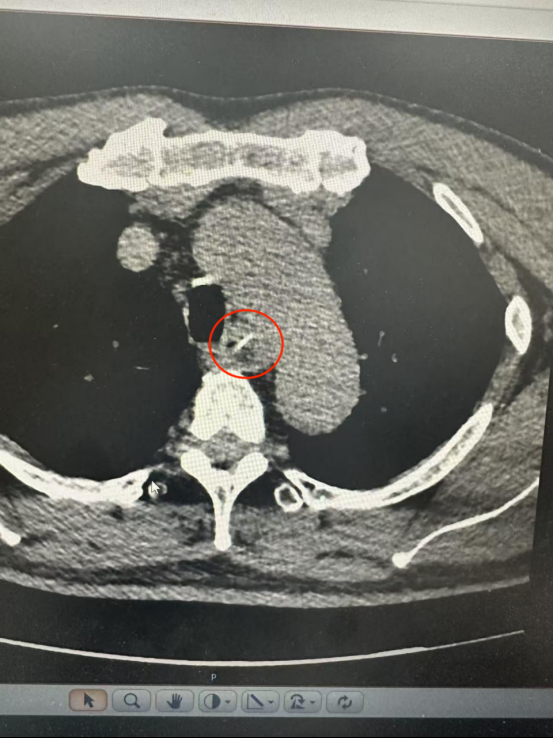

下午6時(shí),程先生匆忙前往湖北航天醫(yī)院急診科就診。醫(yī)生檢查發(fā)現(xiàn)其口咽部及咽喉部未見(jiàn)異物,立即安排胸部CT檢查。

CT結(jié)果顯示一根長(zhǎng)約25毫米的魚(yú)骨卡在食管中段,兩端分別緊貼食管管壁外緣與主動(dòng)脈弓內(nèi)側(cè)。主動(dòng)脈是人體最粗大的動(dòng)脈血管,魚(yú)骨所處位置極為危險(xiǎn)。

根據(jù)CT三維重建結(jié)果,魚(yú)骨緊貼主動(dòng)脈弓但未刺破主動(dòng)脈及食管全層,尖端與主動(dòng)脈切線(xiàn)垂直,呈“一”字型排列。